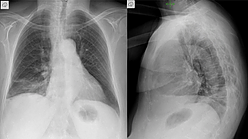

Opacidad en vidrio deslustrado en el lóbulo inferior derecho.

3 días después

Aumento leve de la opacidad en vidrio deslustrado, sin cambios en los otros lóbulos.

aunque la infección por SARS-CoV-2 (COVID-19) se describe por tener un curso rápidamente progresivo, a veces puede manifestarse como vidrio deslustrado que permanece relativamente estable. En este caso, la paciente, a pesar de su edad, permaneció clínicamente estable y fue dada de alta a la cuarentena domiciliaria.